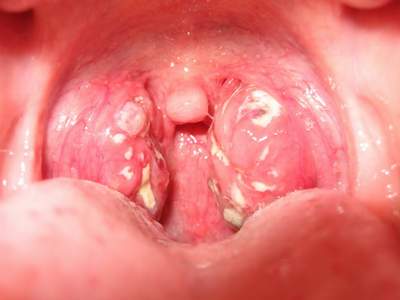

Bạch hầu là một bệnh lây cấp tính gây dịch do corynebacterium diphtheriae gây ra. Các bệnh cảnh lâm sàng thường gặp có thể là bạch hầu thường, bạch hầu họng-thanh quản (croup) và bạch hầu ác tính do vi khuẩn đột nhập qua da và niêm mạc gây ra các giả mạc dai tại chổ bị nhiễm khuẩn (thường là ở hầu họng, thanh quản, mũi, mắt, da hoặc bộ phận sinh dục) từ đó vi khuẩn tiết ra ngoại độc tố vào máu gây nhiễm độc cơ tim, thận các dây thần kinh trung ương và ngoại biên. Chẩn đoán xác định bệnh bạch hầu khi thấy có giả mạc trắng bóng bám chặt vào niêm mạc, giả mạc dai, dính, lan nhanh ở họng và ngoáy rìa giả mạc cấy có vi khuẩn bạch hầu. Trong trường hợp chẩn đoán hoặc nghi ngờ là bạch hầu thì phải được điều trị ngay bằng huyết thanh kháng độc tố bạch hầu (SAD) và các kháng sinh như penicillin hoặc kháng sinh nhóm Macrolides, tỷ lệ tử vong do bệnh bạch hầu có thể từ 5-10%.